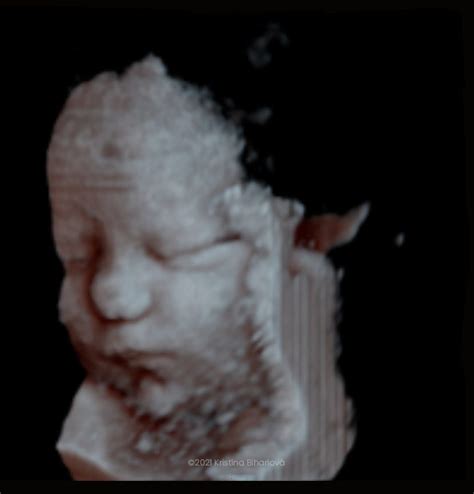

Okrem štandardného 2D ultrazvuku, ktorý poskytuje dvojrozmerný obraz, existujú aj pokročilejšie techniky ako 3D a 4D ultrazvuk. 3D ultrazvuk predstavuje statické zobrazenie plodu v priestore, pričom trojrozmerný obraz sa dosahuje počítačovým spracovaním súboru nakumulovaných 2D obrazov. Táto technika umožňuje získať detailné fotografie vášho bábätka.

Výukový program 4D ultrazvuku: Pochopenie 4D zobrazovania

Ďalšou možnosťou je 4D zobrazenie, ktoré sa od plastického 3D obrazu líši pridaním dimenzie času v podobe pohybu. Snímku vidíte v priamom prenose, môžete sledovať, ako sa dieťa hýbe, zíva, či dokonca naťahuje. Táto technika umožňuje vidieť dieťa v reálnom čase a sledovať jeho mimiku. Aj keď 3D ultrazvuk nie je vždy úplne zreteľný a "vydarený", je medzi budúcimi mamami pomerne obľúbený, pretože poskytuje krásne spomienky a detailný pohľad na dieťatko. Lekár vám môže z takéhoto vyšetrenia dokonca vytlačiť 3D fotografiu dieťatka.

MUDr. Kristína Bihariová, gynekologička a pôrodníčka vo Zvolene, sa špecializuje na moderné 3D ultrazvukové vyšetrenia. Svoje bohaté skúsenosti a individuálny prístup ku každej pacientke využíva na to, aby budúcim mamičkám priniesla detailný a nezabudnuteľný pohľad na ich bábätko. Jej vzdelanie zahŕňa štúdium na 2. lekárskej fakulte Univerzity Karlovej v Prahe, atestácie v odbore gynekológia a pôrodníctvo a špecializačnú atestáciu z ultrazvukového zobrazenia v gynekológii a pôrodníctve. Je držiteľkou certifikátov Fetal Medicine Foundation v oblasti skríningov prvého trimestra, skríningu preeklampsie a skríningu rizika predčasného pôrodu. Svoje pracovné skúsenosti nadobudla na renomovaných pracoviskách v Prahe a vo Zvolene.